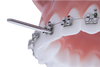

Are you tired of adhesive flashes around brackets’ wings?

You cannot make the perfect ligature tie?

You have no time to place a new bracket in the busy afternoon?

- A special design to clean any excessive adhesive under the wings without damage the brackets. (when used properly with light force).

- May be used with SS and ceramic brackets.